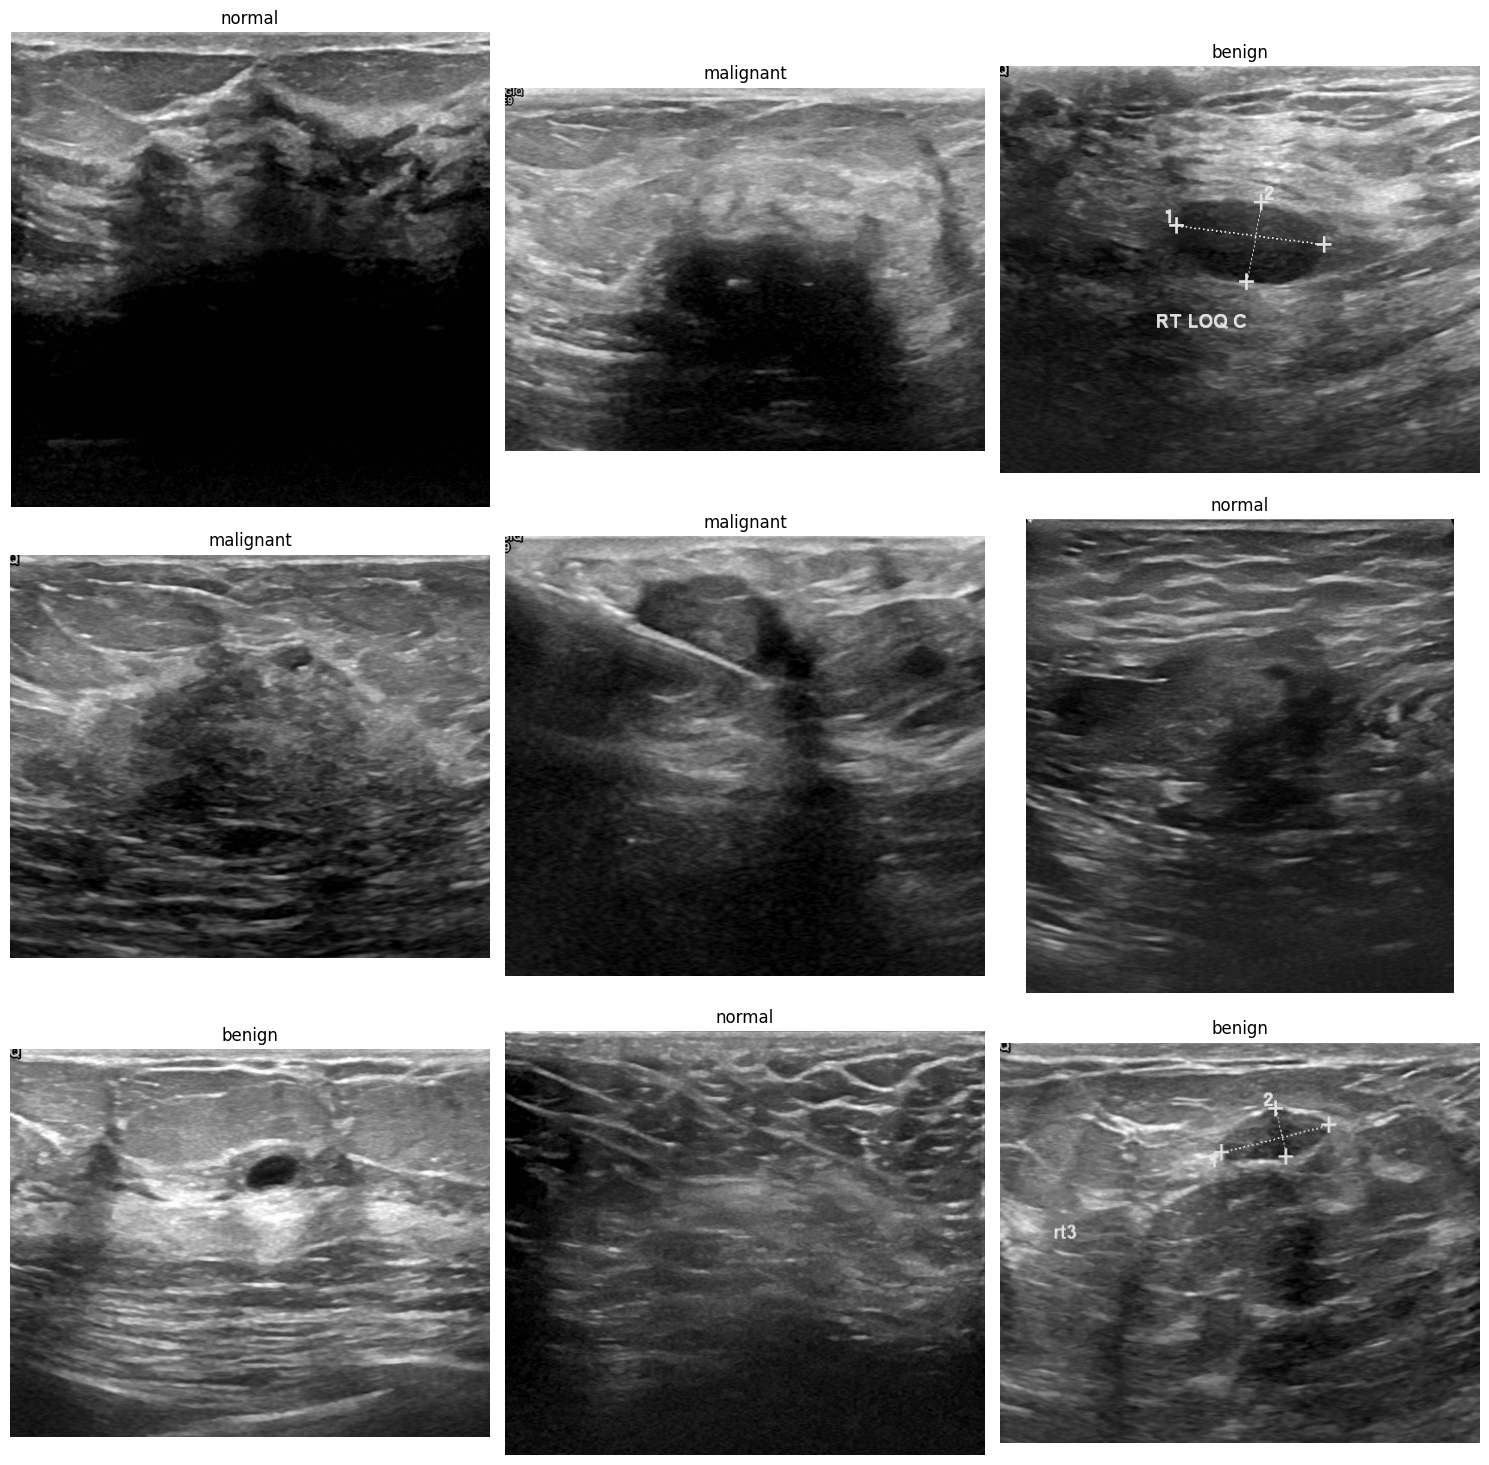

The custom dataset is hand-made, containing 780 images with 3 classes (benign, malignant, normal).

Let’s show one image from each class from dataset.